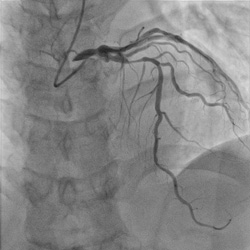

血管造影装置装置 「Alura Xper FD10/10(flexvision)」導入

この装置により、X線の透視や撮影画像による心臓等の血管を観察しながら血管造影、血管内治療を行うことができます。

次の3つが特長です。

まず、フラットパネル検出器というフルデジタルのX線検出機構を採用しています。従来のアナログシステムより良好な画質が安定して得られ、また、効率良くX線を使用するため患者さんの被ばくも確実に減らせます。

次にバイプレーンと言って、同時に2方向からの透視・撮影が可能です。2方向から同時観察することで血管等をより立体的に詳しく見ることができます。また、1回の造影剤注入により2方向からの画像が得られる為、造影剤量を減少させ腎臓などへの負担も軽減されます。

Flexvisionと呼ばれる56インチ大画面LCDモニターにより血管等が非常に観察し易くなりました。また、血管内超音波や心電図などの治療工程で重要な患者さんに纏わる画像情報も簡単に切り替え表示でき、手技に沿って色々な情報を確認しながら血管内治療ができるようになりました。

以上のような特長により今まで以上に患者様の負担を減らしつつ、より高度な血管造影、血管内治療が可能となりました。

RCALCA